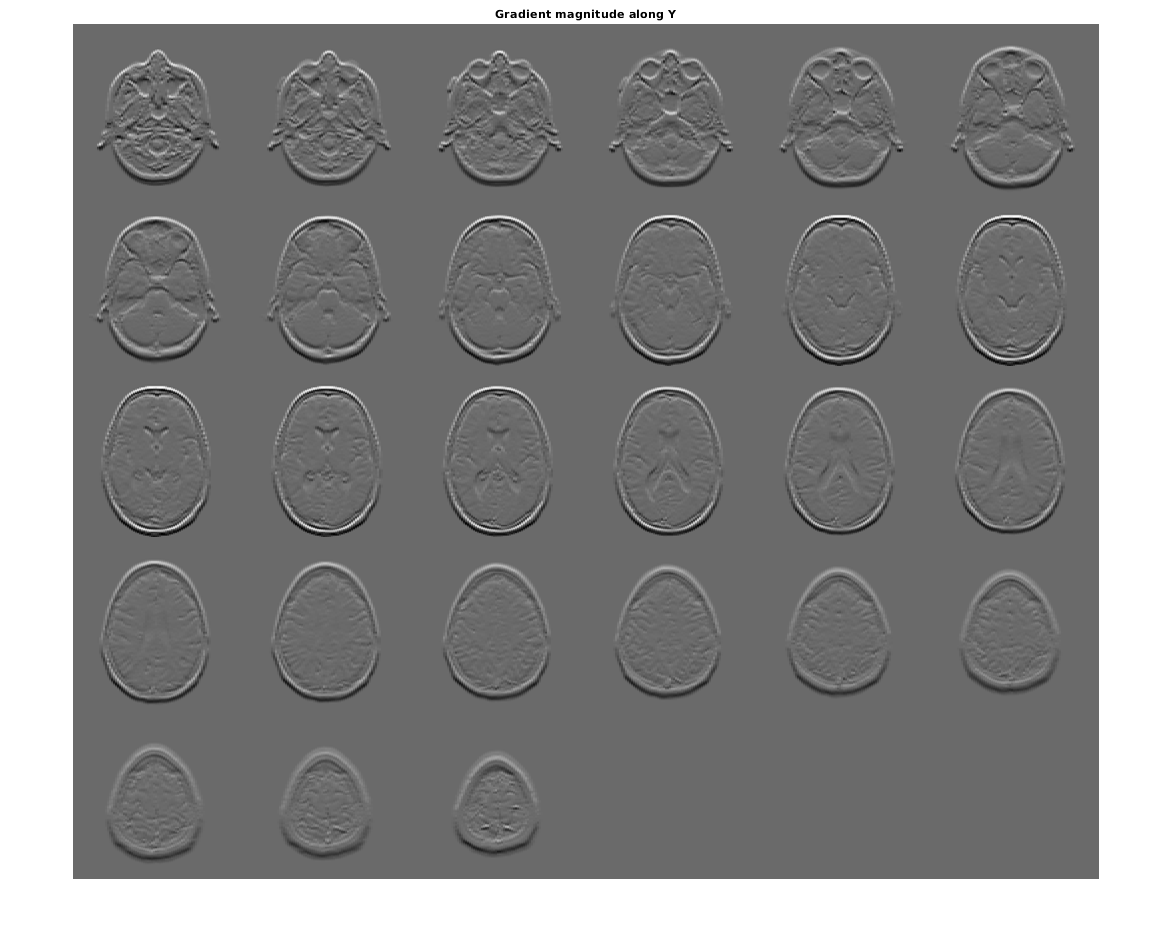

figure, montage(reshape(Gy,sz(1),sz(2),1,sz(3)),'DisplayRange',[])

title('Gradient magnitude along Y')